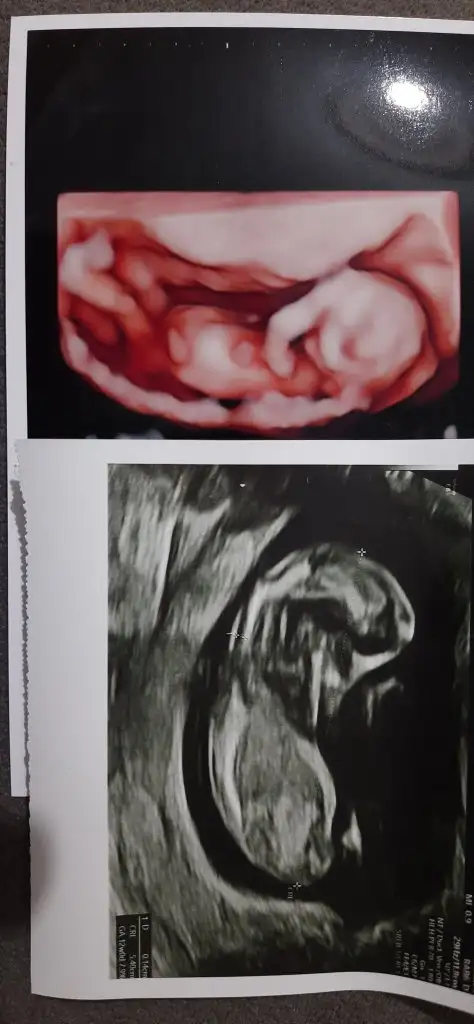

Kızlaar ben geldim . Kontrol güzel geçti doktorumu sevdim ilgiliydi baya ama 5 haftada bir çağırıyomuş çok uzun geldi ya. Ense kalınlığı burun kökü vs baktı normal dedi çok şükür öyle deyince ikili testi istemedim kendi de zorlamadı zaten. Size fotoları bırakıyorum doktor cinsiyet tahmininde bulundu bir de sizden tahmin alayım dedim

Eklentiler

• 20221011_195637.webp

24 KB · Görüntüleme: 93

Güzel haberlerle gelmişsn canım şükür hersey yolunaymıs, veee bence kız ya cok kibar duruyo

Kız mı dedi? Çok merak ettim benim bebeğimin karnı çok çıkık duruyordu. Ama bir yorum yapmadı doktor. Bunda daha kibar bir görüntü var. o yüzden kız dedim ben de

Ama bak canım benim bir tane daha var bunda karnı daha çıkık seninkine göre yine de düşük mü bilmiyorum da

Maşallah canım ne tatli görüntüler cok sevindim herseyin yolunda olmasina banada selvi boylu Bi kizce gibi geldi